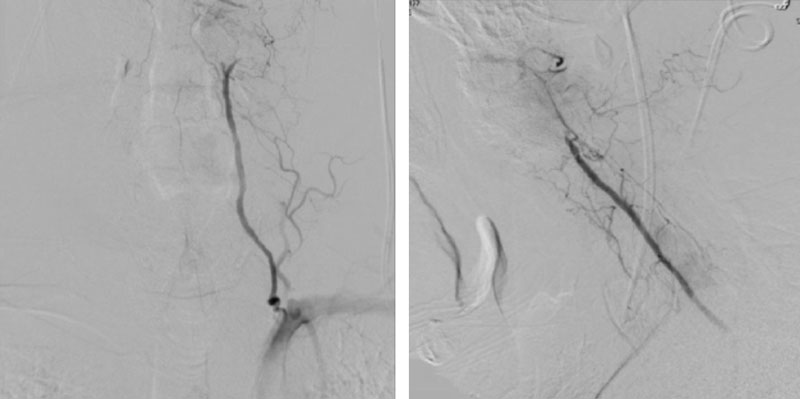

We performed conventional catheter angiography with provocative testing to reproduce his symptoms. The right Vertebral Artery is the codominant primary supply to the basilar circulation with reflux into the distal left Vertebral Artery that is occluded (Figure 3).

During neutral positioning, the vertebrobasilar circulation fills briskly from the Right Vertebral Artery. (Figure 4)